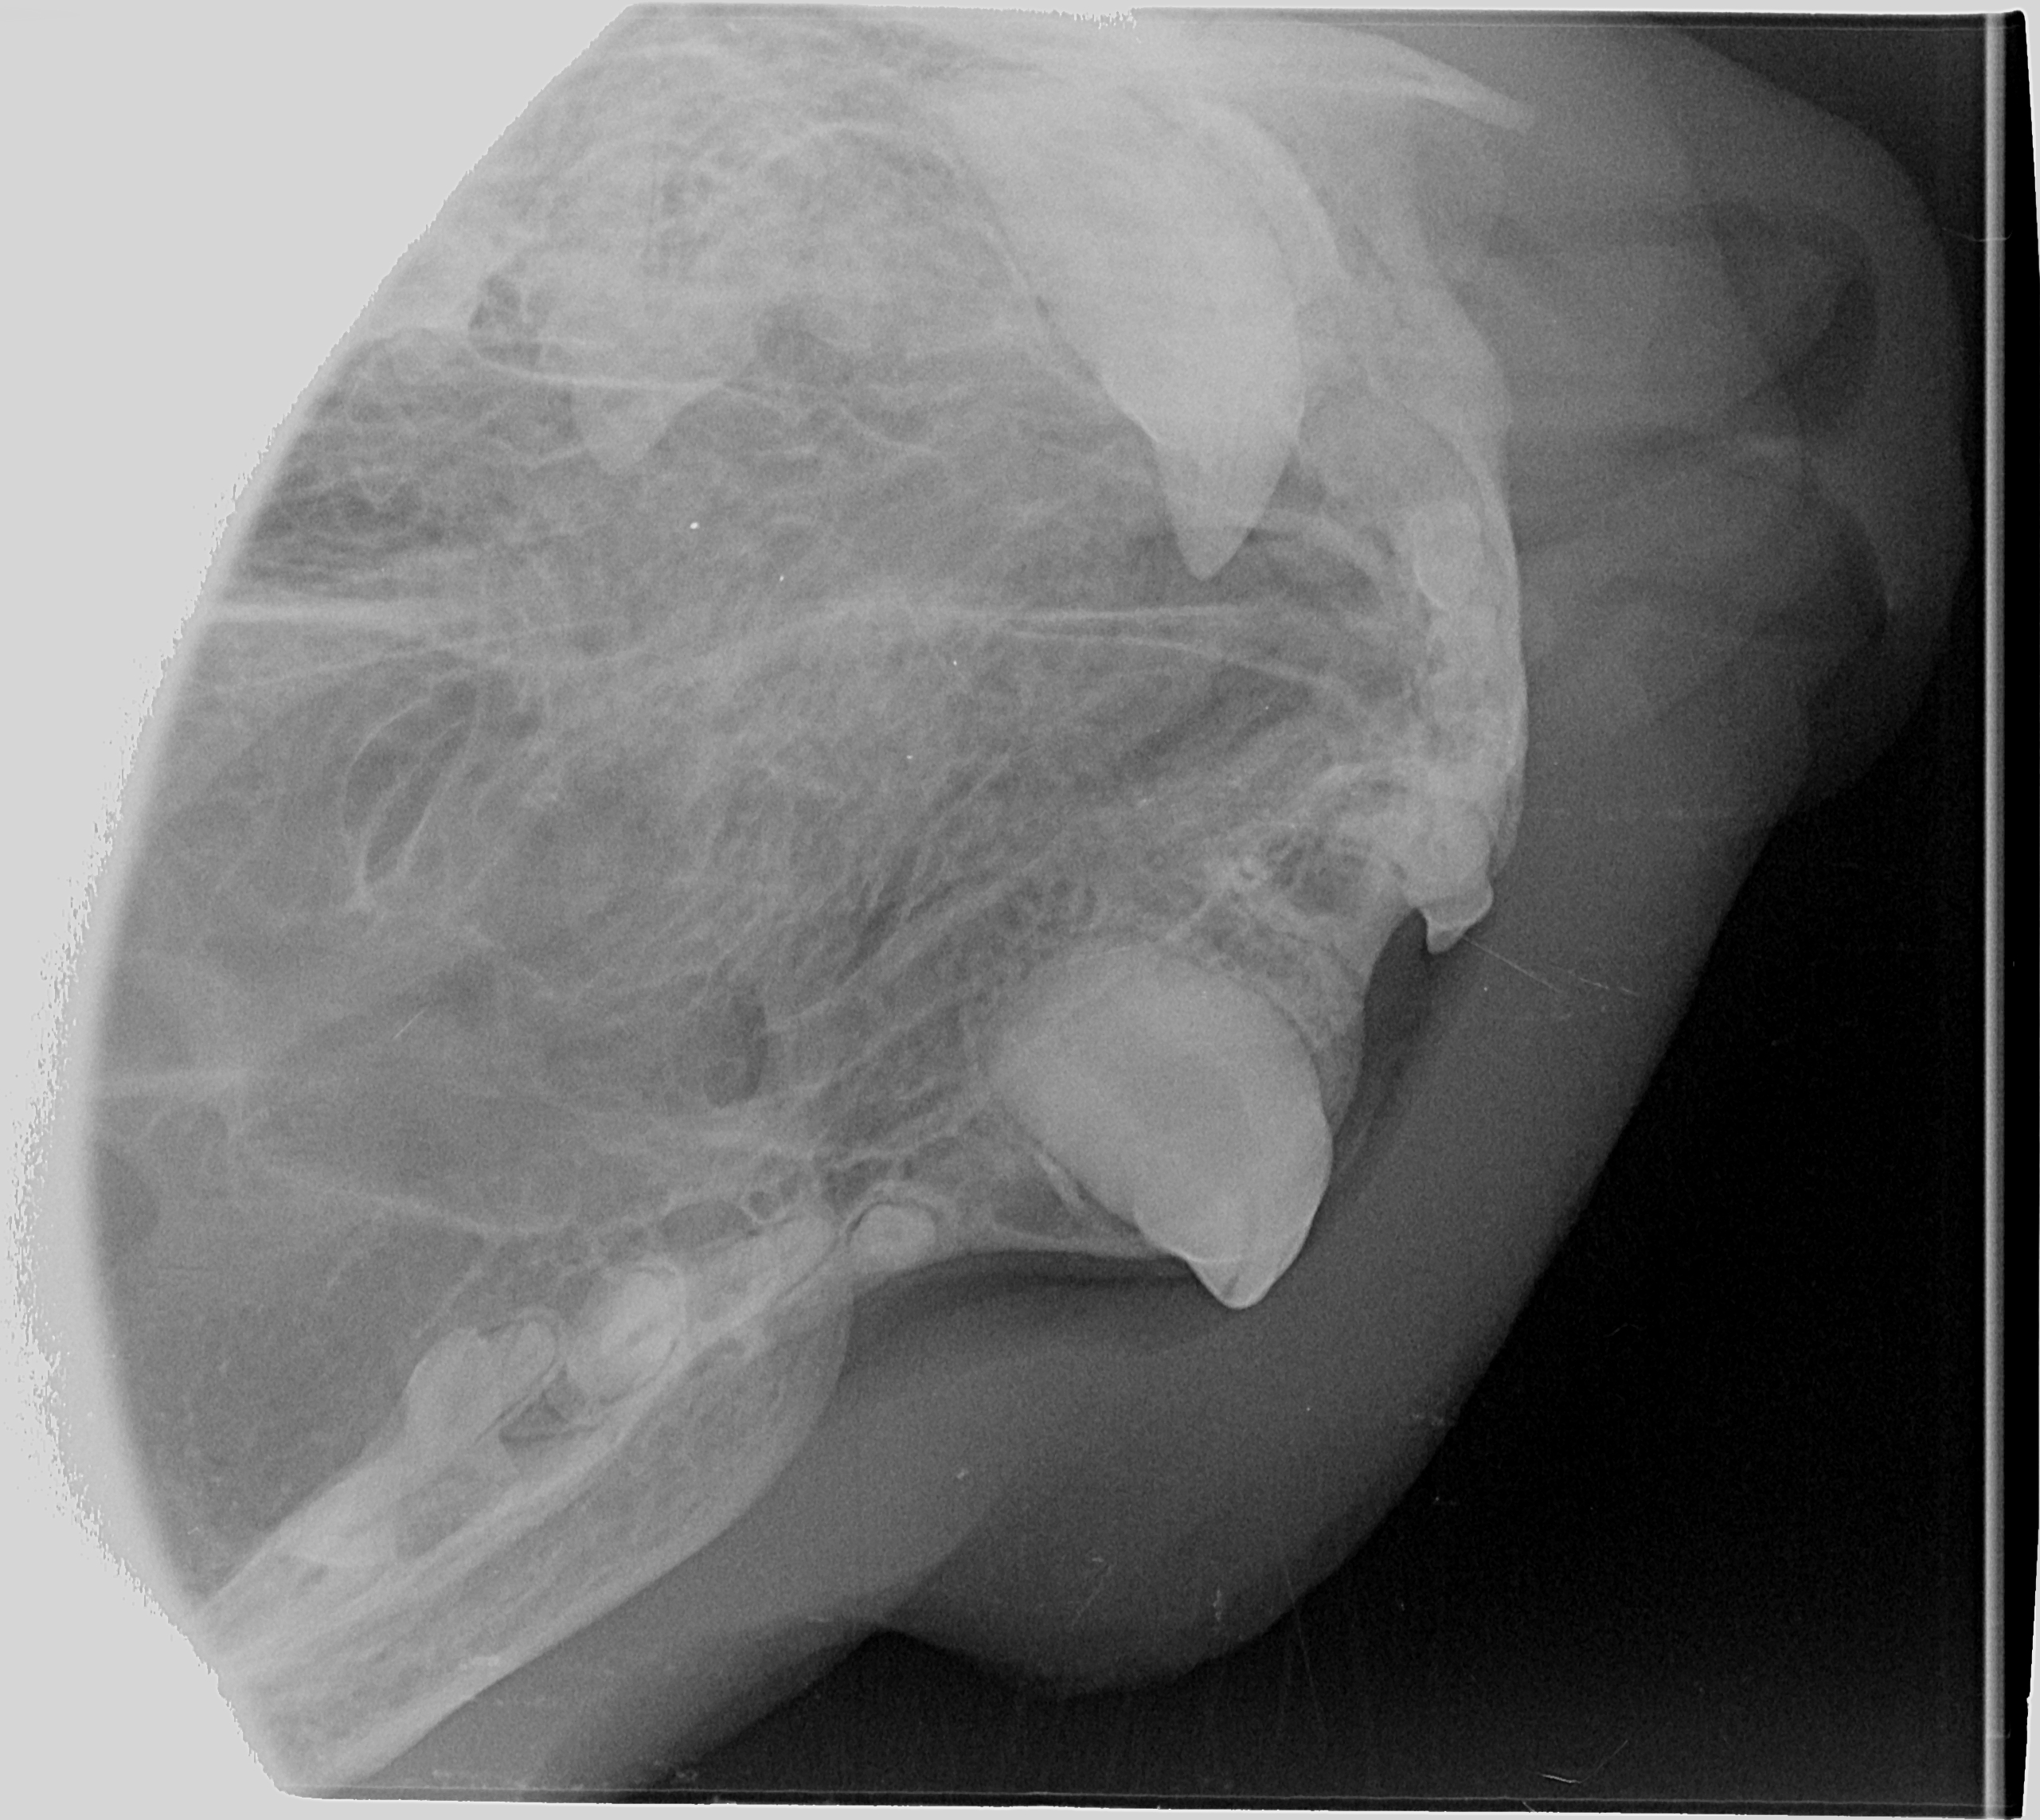

Kissan hampaat voivat näyttää päällisin puolin ihan hyvältä, mutta hampaiden juurissa voi olla piileviä ongelmia. Ainoa tapa selvittää, ovatko hampaat oikeasti kunnossa, on ottaa hammasröntgen.

IC Moggi Sikuri Sakari(Kilju) piipahti jo jonkin aikaaa sitten Amyvetissä hammahuollossa ja samassa kalusto pääsi kuviin. Tulos oli juuriaan myöten terveet hampaat. Hammaskiven poistoa pienesti ja ohjeeksi harjailla hampaita ahkerasti.

Ohessa muutama kuva malliksi.